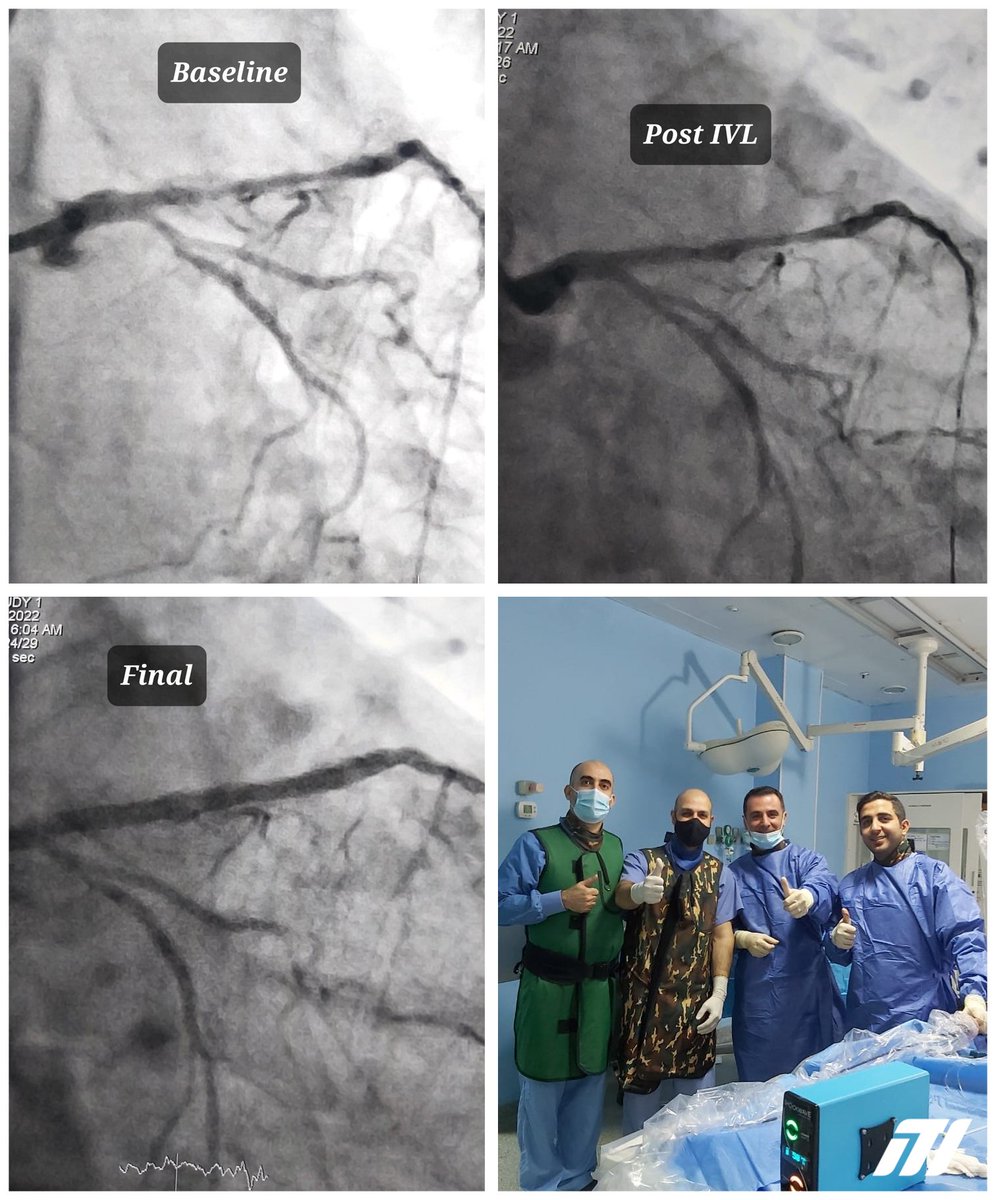

33mm of heavy calcium taking the LAD from the proximal to the mid segment was treated with @ShockwaveIVL by Dr. Gilbert Abou Nader at MEIH

Heavily #calcified proximal LAD treated with @ShockwaveIVL C2 by Major Dr. Hassan Abdel Sater, Head of interventional cardiology department at Military Hospital.